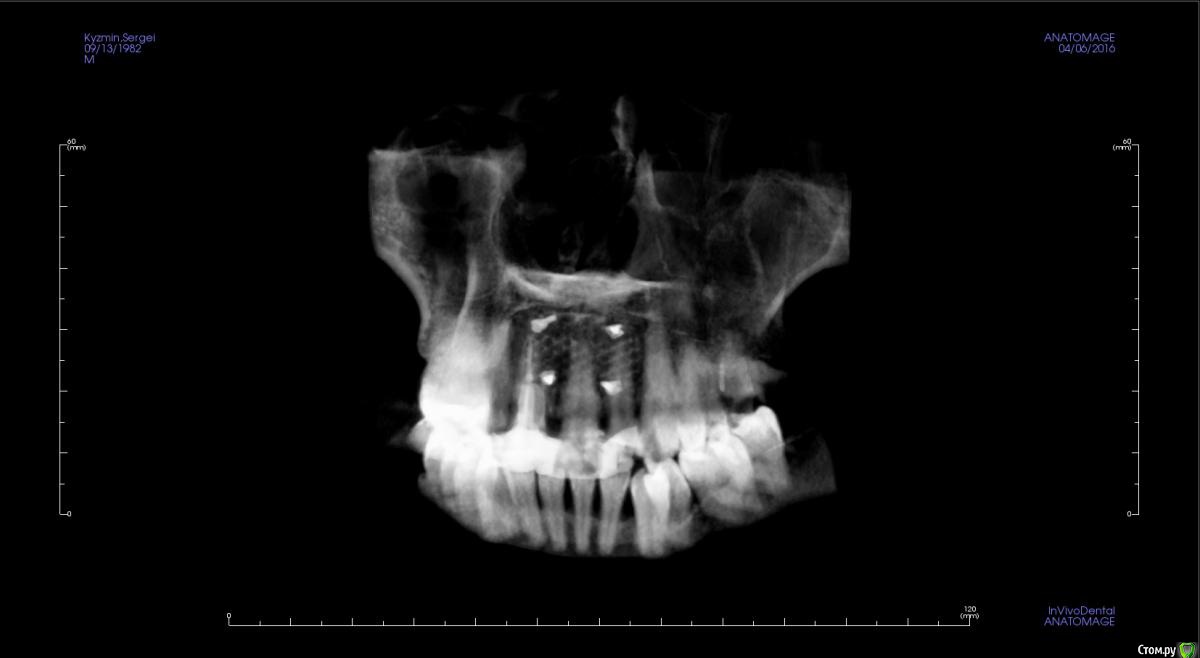

kamranchick Опубликовано 17 апреля, 2016 Поделиться Опубликовано 17 апреля, 2016 Пришел пациентДок привет, что то зуб шатается, можно ли его оставить, вот такие дела)как бы вы поступили бы? Ссылка на комментарий

Bier Опубликовано 17 апреля, 2016 Поделиться Опубликовано 17 апреля, 2016 репозиция и зашинировал бы просто брекетами 4 Ссылка на комментарий

Fibez Опубликовано 17 апреля, 2016 Поделиться Опубликовано 17 апреля, 2016 репозиция и шина ортодонтической проволкой на композит с заходом на 2 зуба слева-справа. срок на месяц. щадящая диета. наблюдение в динамике за витальностью. 6 мес, год. Ссылка на комментарий

dantist_movani Опубликовано 27 апреля, 2016 Поделиться Опубликовано 27 апреля, 2016 Пришел пациентДок привет, что то зуб шатается, можно ли его оставить, вот такие дела)как бы вы поступили бы?1)проверил бы на витальность2)Репозиция и шинирование орто ретейнером с жидкотекучим композитомпохожая ситуация была год назад, правда отлом кортикалки не столь значительный был. Ретейнер снял через 6 мес, все Ок, зуб не почернел♿, эод -8 в дуге, пац очень доволен Ссылка на комментарий